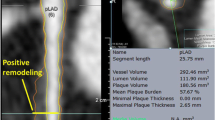

Arterial remodeling is another major determinant of plaque morphology and possible progression. Remodeling is an adaptive mechanism which reflects the ability of the vascular wall to adjust its dimensions in response to plaque growth or flow alterations. Positive or expansive remodeling denotes an increase in arterial dimensions, while negative or constrictive remodeling signifies that the arterial size decreases [16]. Compensatory expansive remodeling, as first highlighted by Glagov and colleagues in 1987 [17], is a process whereby the outer arterial wall enlarges to accommodate the plaque present within the arterial wall so that the lumen dimensions remain unchanged and distal blood flow is preserved. Excessive expansive remodeling, in contrast, is associated with highly inflamed atheroma, where the activated leukocytes elaborate plaque-degrading collagenases and elastases which disrupt the plaque structural integrity and lead to a focal excessive enlargement of the lumen and the arterial wall. These areas of excessive expansive remodeling have been consistently associated with high-risk plaque features leading to acute plaque rupture and acute coronary syndromes [18].

Arterial remodeling of individual plaques seems to be very dynamic over time, according to experimental data from animal studies. A considerable percentage (∼75 %) of ostensibly high-risk TCFAs in human arteries may heal and become quiescent during the natural course of atherosclerosis, possibly because of arterial remodeling that may reduce the local pro-inflammatory low endothelial shear stress (ESS) environment, underscoring the complexity of pathophysiologic mechanisms leading to clinical events (Fig. 1) [5••, 26••, 27]. Furthermore, it has recently become clear that the phenotypic manifestations of atherosclerosis are not uniform even along the length of an individual plaque, but are very heterogeneous with a variety of plaque morphologies, remodeling characteristics, and local hemodynamic environments along their length, and the longer the plaque length the more heterogeneous the various plaque characteristics along that plaque (Fig. 2) [28].

Heterogeneity of local plaque characteristics within individual human plaques. Coronary angiography and IVUS-derived 3D artery reconstruction was performed in 219 patients of the PREDICTION study, and 371 plaques were identified (adapted from Reference [28], with permission). a Arterial remodeling patterns per plaque. The number of arterial remodeling patterns in an individual plaque progressively increased as the plaque became longer. b. ESS patterns per plaque. The number of ESS patterns in an individual plaque progressively increased as the plaque became longer

Plaque Heterogeneity Along Individual Plaques

There is substantial heterogeneity in plaque composition and morphology within individual coronary atherosclerotic plaques [54]. An early IVUS study identified heterogeneity in plaque composition in nearly 9 out of 10 plaques, while the remodeling pattern was heterogeneous in about one fourth of plaques [6]. A recent study from the PREDICTION (Prediction of Progression of Coronary Artery Disease and Clinical Outcomes Using Vascular Profiling of Shear Stress and Wall Morphology) study detailed three-dimensional (3D) assessments of human coronary arterial and plaque morphology and confirmed the above findings, showing that a considerable proportion of plaques exhibit a combination of two or three remodeling patterns, as well as ESS profiles, concurrently along their length. Coronary plaque length is also highly variable ranging from 9 to 30 mm in various proportions [28]. The consequence of this plaque heterogeneity is that at any given point in time, different regions of a plaque can exhibit different stages of progression and development and, accordingly, different magnitudes of pathobiologic stimuli for further atherosclerotic progression or quiescence [28, 40, 55, 56]. These different risk profiles along the course of an individual plaque also change markedly over time. A simple risk assessment of an individual plaque at a single point in time based on the plaque imaging characteristics at the minimal lumen diameter, which is the usual clinical measure, may consequently seriously misrepresent the actual risk of that plaque. The actual morphological and risk complexity constitutes an important challenge for cardiovascular imaging modalities employed for the risk-stratification of CAD.